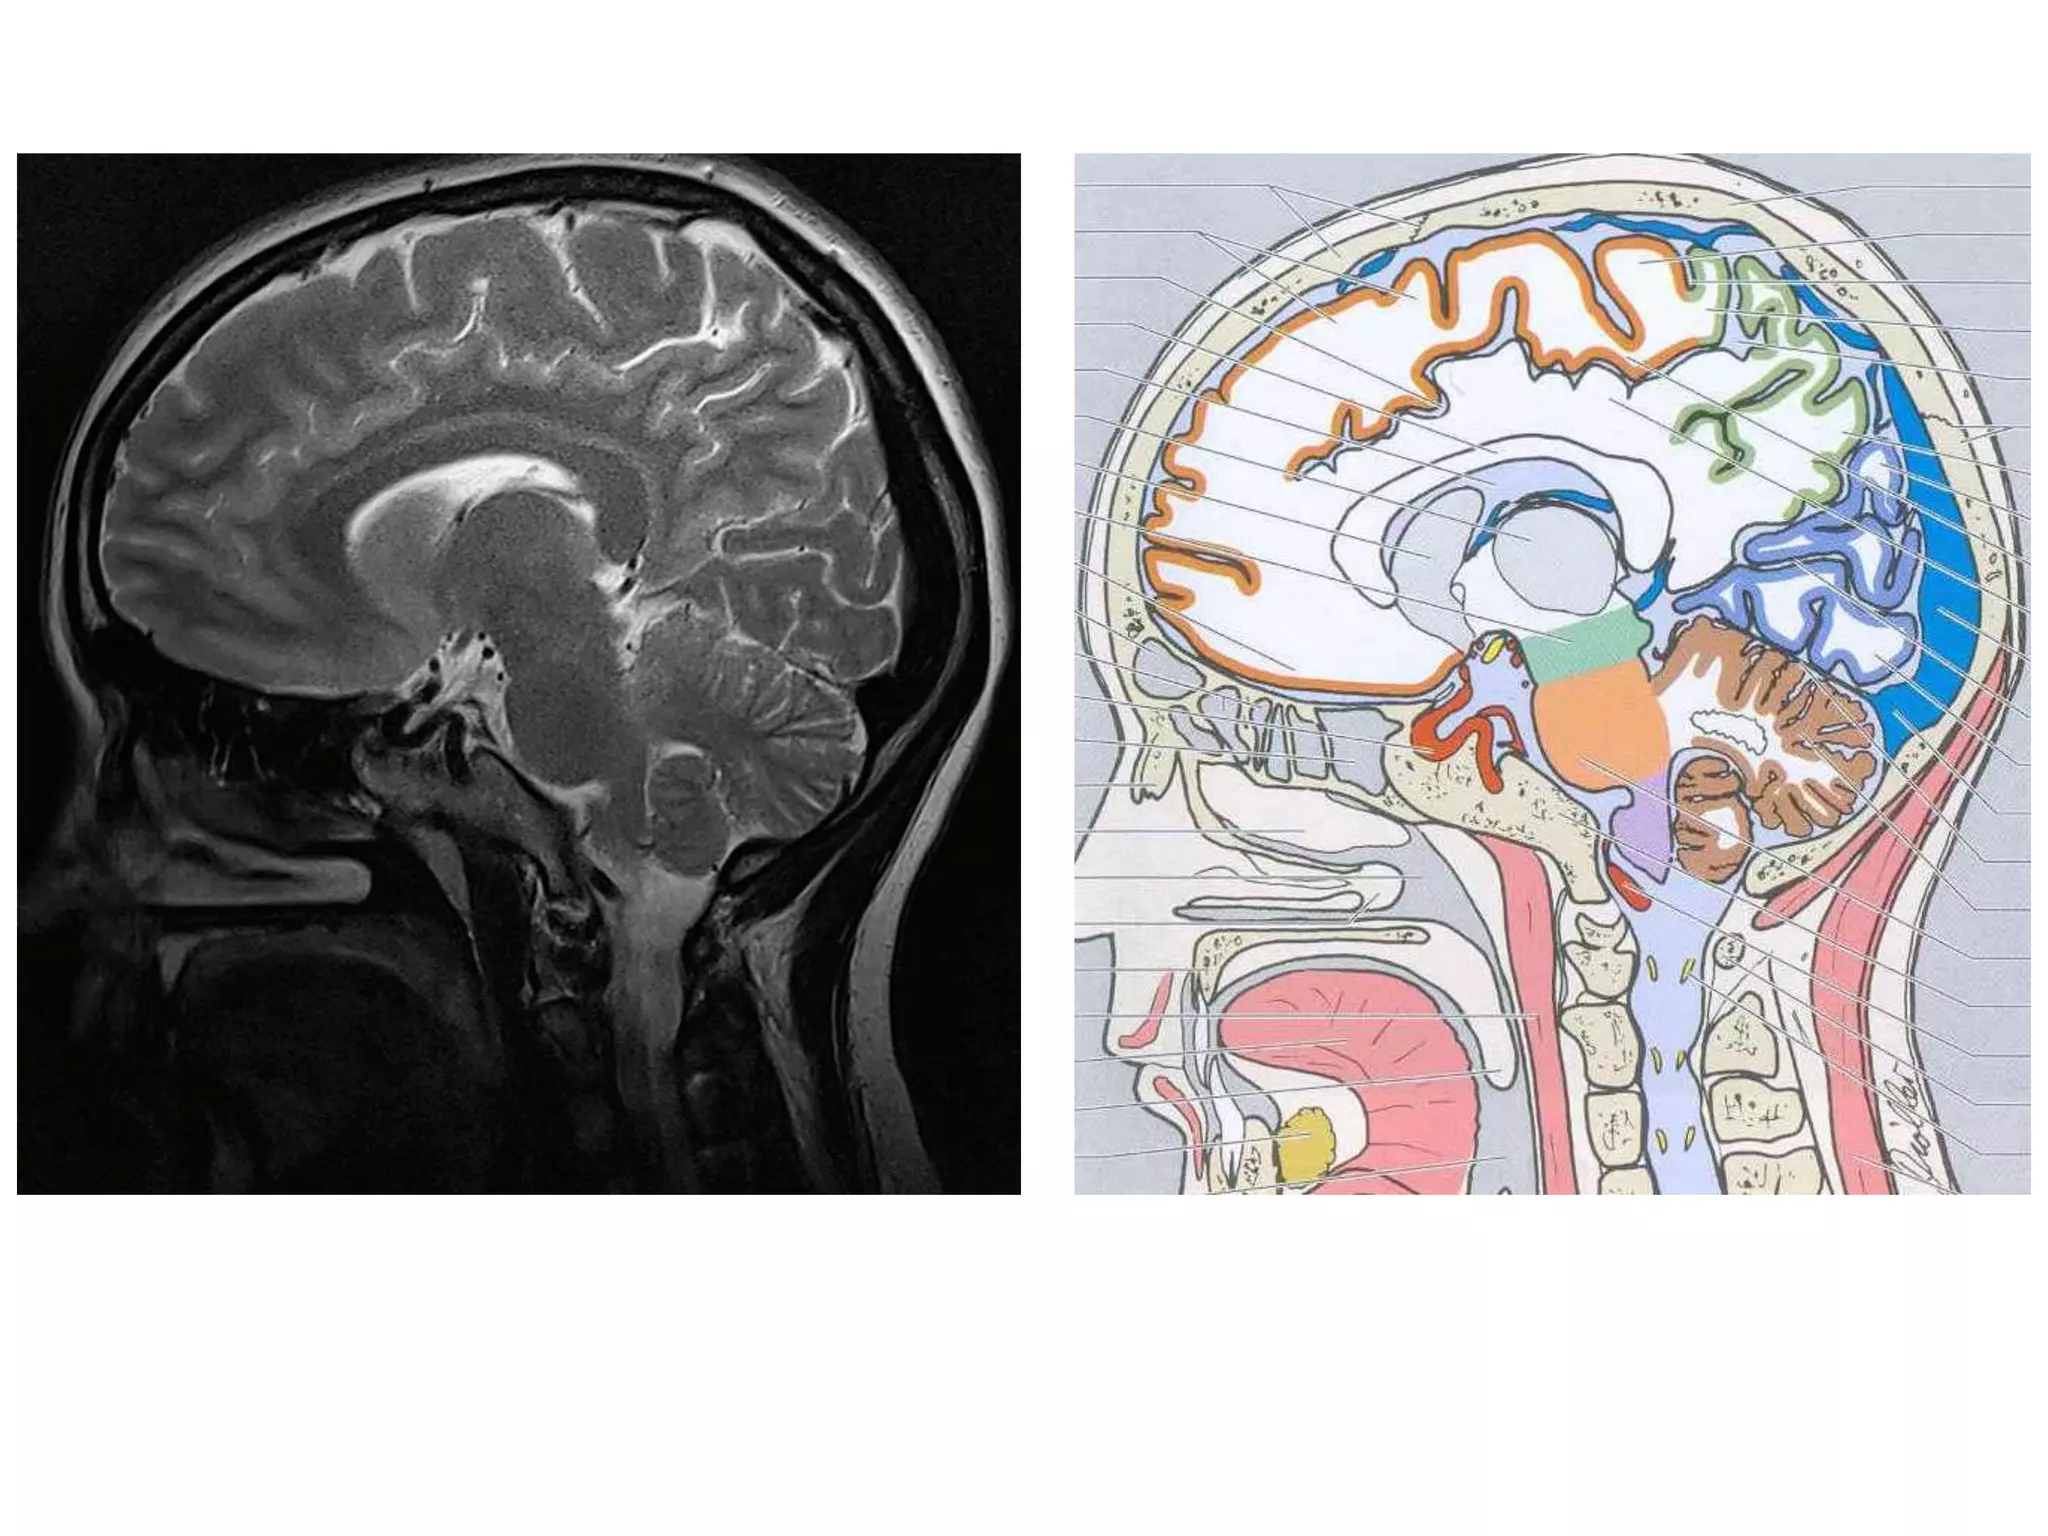

• Anatomy of cerebral hemispheres and mid brain – T1 W

MRI.

• Internal grey - white matter areas – T2 W MRI.

• Saggital and Coronal T1 weighted MRI – accurate

assessment of ventricles and C. callosum

• Mid Saggital section – for shape and configuration

of Aqueduct of Sylvius.